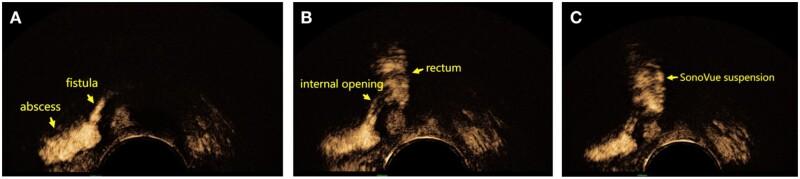

Accurate preoperative evaluation of fistula-in-ano can guide the choice of surgical procedure and may improve healing rates. This prospective study aimed to evaluate the accuracy of conventional 3D transperineal ultrasound (3D-TPUS) compared with SonoVue (SVE)-enhanced 3D-TPUS for the detection and classification of anal fistula.

In this prospective study, 3D-TPUS reconstructions were performed before and after SVE enhancement in 60 patients with fistula-in-ano who intended to undergo surgery at the Department of Anorectal Surgery, Qilu Hospital, Cheeloo College of Medicine, Shandong University (P. R. China) between January 2021 and October 2021. Accuracies of anal fistula classification, complexity classification, detection of anal fistula branches, and detection of internal opening between 3D-TPUS and SVE 3D-TPUS were compared based on a reference standard-intraoperative findings.

This study enrolled 60 patients (mean age, 37.1 ± 11.4 years; mean follow-up, 9 ± 3 months). Intraoperative findings showed that the fistula type was intersphincteric in 23 patients (38.3%), trans-sphincteric in 35 (58.3%; 12 high and 23 low), and suprasphincteric in 2 (3.3%). Moreover, 68 internal openings were found. Compared with the accuracy of 3D-TPUS, that of SVE 3D-TPUS was similar in fistula classification [95.0% (57/60) vs 96.7% (58/60), =0.392], but significantly higher in internal opening evaluation [80.9% (55/68) vs 97.1% (66/68), =0.001], complexity classification [85.0% (51/60) vs 98.3% (59/60), =0.018], and detection of fistula branches [70.4% (19/27) vs 92.6% (25/27), =0.031].

SVE 3D-TPUS may be a useful examination for patients with perianal fistulae because of its high accuracy and consistency with intraoperative findings, especially in complex fistula-in-ano and difficult cases.